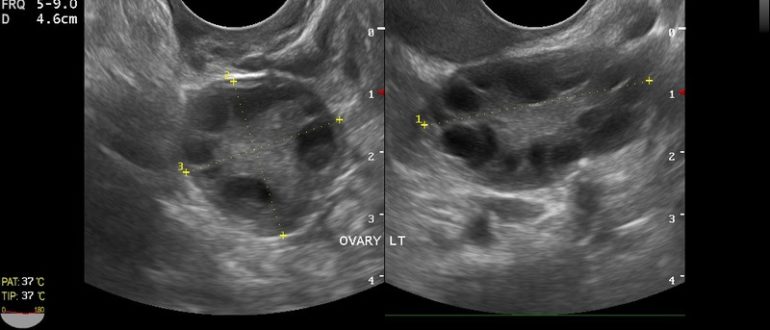

Мультифолликулярные изменения яичников

Основные признаки мультифолликулярных яичников (МФЯ) – информация для пациентов — клиника «Добробут» Мультифолликулярные яичники – состояние, при котором в половых железах созревает 10 и более фолликулов (в норме…

Мультифолликулярный яичник или поликистоз?

Мультифолликулярные или поликистозные яичники Мультифолликулярными яичниками называют такие яичники, у которых одновременно увеличено несколько фолликулов (12 и более штук). Если в первую фазу цикла у женщины на УЗИ…